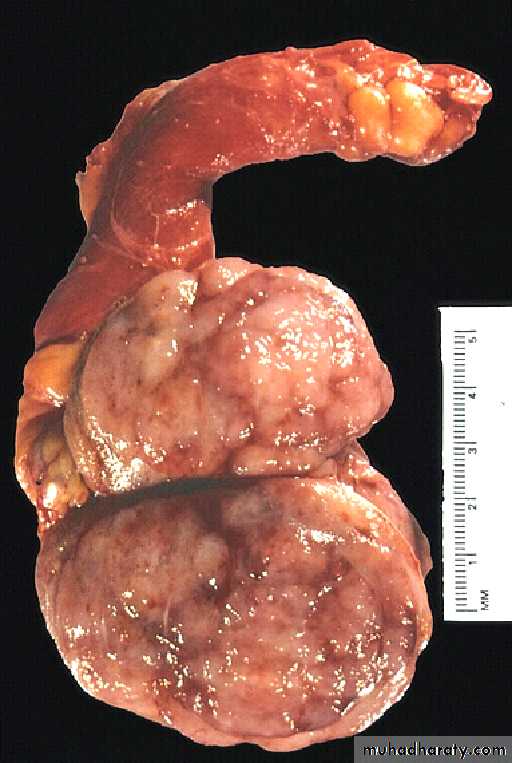

Seminoma testis gross

A small rim of remaining normal testis appears at the far right. The tumor is composed of lobulated soft tan to brown tissue.Seminoma

Classic seminoma:- about 90% of all seminomas. On gross examination, the tumor is solid, gray-white, poorly demarcated growth that bulges from the cut surface of the testis. The tumor may replace the entire testis in more than half of the cases.